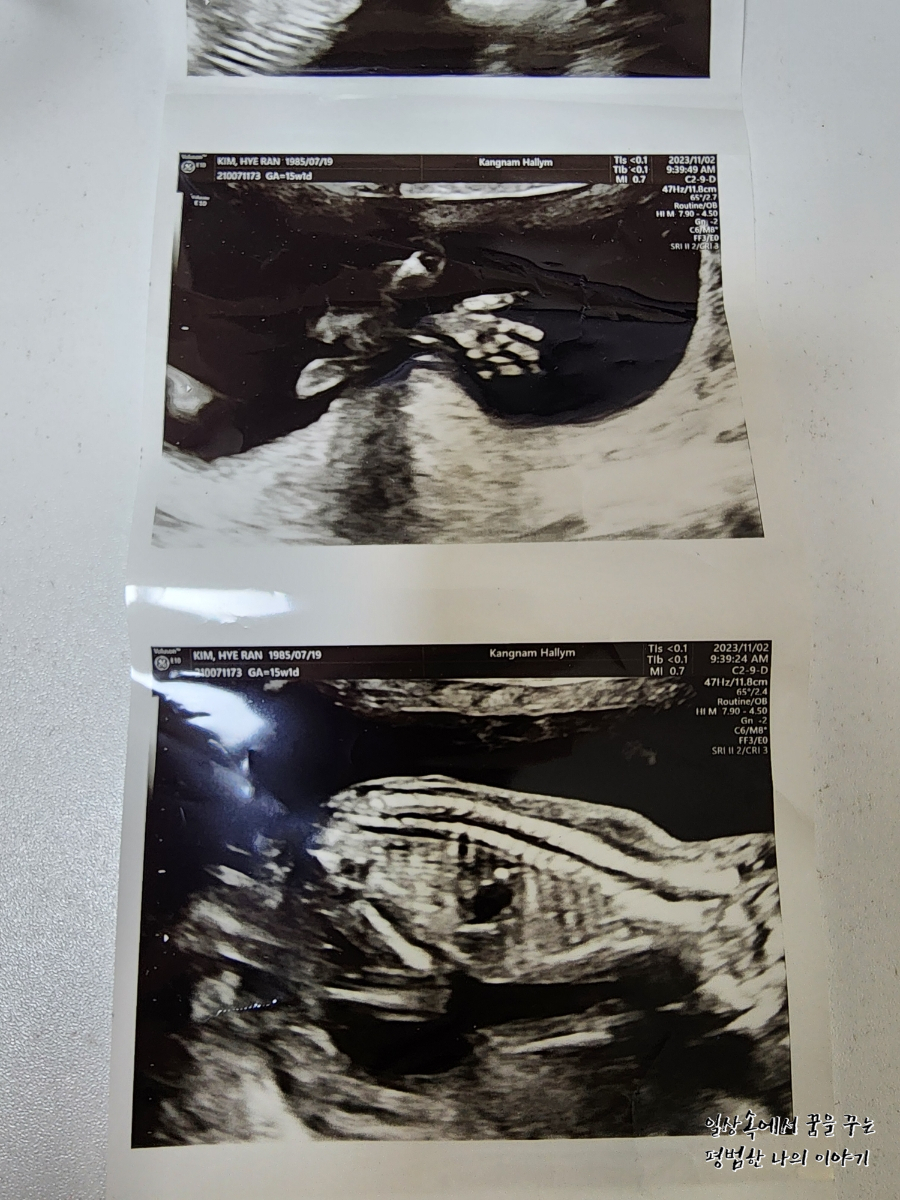

2023년 11월 2일(목요일)

BPD(Biparietal Diameter, 위에서 볼 때 태아 머리 단면의 가장 긴 길이): 3.17cm

HC(Head Circumference, 태아 머리둘레): 11.53cm

AC(Abdominal Circumference, 배 둘레): 9.74cm

EDD(Expected Date of Delivery, 출산 예정일): 2024년 4월 21일

FL(Femur Length, 허벅지뼈 길이): 1.81cm

GA(Gestational Age, 임신 주차): 15주 차 1일

EFW(Estimated Fatal Weight, 태아 예상 체중)=EBW(Estimated Body Weight):

Cereb(Cerebelleum, 소뇌 크기): 14.66mm

FHR(Fetal Heart Rate, 심장박동 수): 154bpm

CL(Cervical Length, 자궁경부 길이): 정상

AF(Amniotic Fluid, 양수): 정상

3주 만에 방문한 병원에서 이번에는 2차 기형아 검사를 했다. 나는 이미 1차 기형아 검사를 니프트로 했기 때문에 2차 기형아 검사로 신경관 결손 검사만 하면 되었다. 신경관 결손 검사도 니프트와 마찬가지로 피검사로 가능하다. 참고로 검사 결과는 1~2주 안에 나온다고 한다. 병원에 검사 결과를 듣기 위해 방문하는 게 번거로워 전화로 결과를 안내받기로 했다. 나는 정확히 딱 2주 뒤인 11월 16일에 전화로 검사 결과를 알려주셨는데 다행히 정상이었다.(내가 다니고 있는 강남성심병원 산부인과 기준) 12주 때와 마찬가지로 레오나가 너무 활동적이라 자세를 너무 자주 바꾸는 바람에 성별을 정확하게 알기는 어려웠지만 딸일 확률이 높다고 하셨다. 딸에서 아들로 반전되는 경우가 많다고 하니 좀 더 정확한 결과를 위해 다음번 진료 때를 기다려보기로...